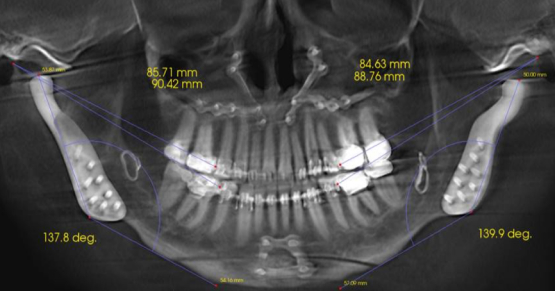

While the etiology of Class V lesions is a frequent topic of debate, generally citing occlusal stress (abfraction), abrasion (tooth brush and toothpaste), and finally corrosion (acid), the one thing I can tell you about this patient is that occlusal stresses do not cause his lesions. He actually has a premolar open bite; his anteriors and molars are all occluded, but there is no premolar contact, no matter how he moves.